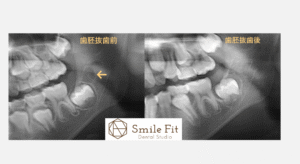

下のレントゲン写真は、**歯胚抜歯(しはいばっし)を行う前と、術後1年後の様子を比較したものです。

ご覧のとおり、第2大臼歯の萌出方向(生えてくる角度)**が大きく変化しているのがわかります。

歯胚抜歯を行うことで、奥から生えてくる歯が手前の歯を押す力を軽減し、

その結果、**歯の傾斜や前歯部のガタつき(叢生)**を予防することができます。

つまり、「将来の歯並びを乱す原因」を早期に取り除くことができるのです。

さらに、歯が正しい位置と方向から生えてくることで、

噛み合わせのバランスや顎の成長方向もより自然で機能的になります。